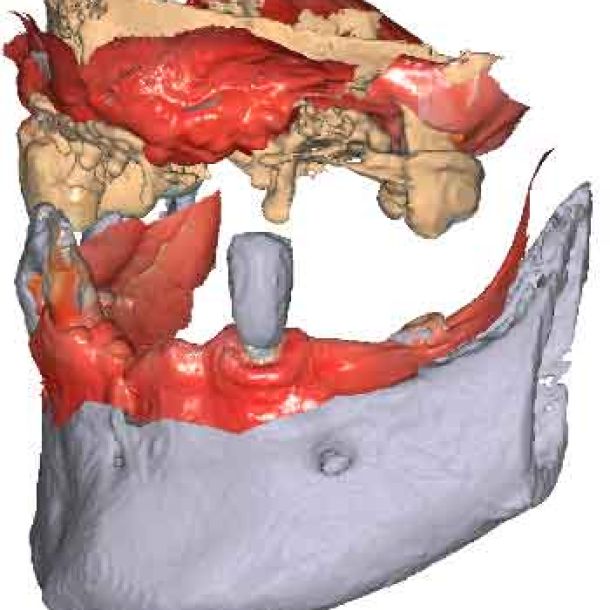

Lorsque les scans IOS traditionnels manquent de références nécessaires, les données du CBCT peuvent servir d'alternative viable. En utilisant les fichiers du CBCT, le clinicien peut établir des références anatomiques précises pour la planification du traitement.

Pour pouvoir utiliser les données CBCT comme modèles initiaux, nous devons transformer le fichier DICOM en un fichier STL. Découvrez-en plus sur la segmentation CBCT et son utilisation dans TWIM ci-dessous.

En important les fichiers DICOM du patient au lieu des scans IOS, les cliniciens peuvent enregistrer le mouvement de la mâchoire, facilitant ainsi la planification précise du traitement.

Importez les modèles CBCT segmentés en tant que modèles initiaux dans TWIM

Sélectionnez 4 points virtuels sur la mandibule du modèle osseux importé